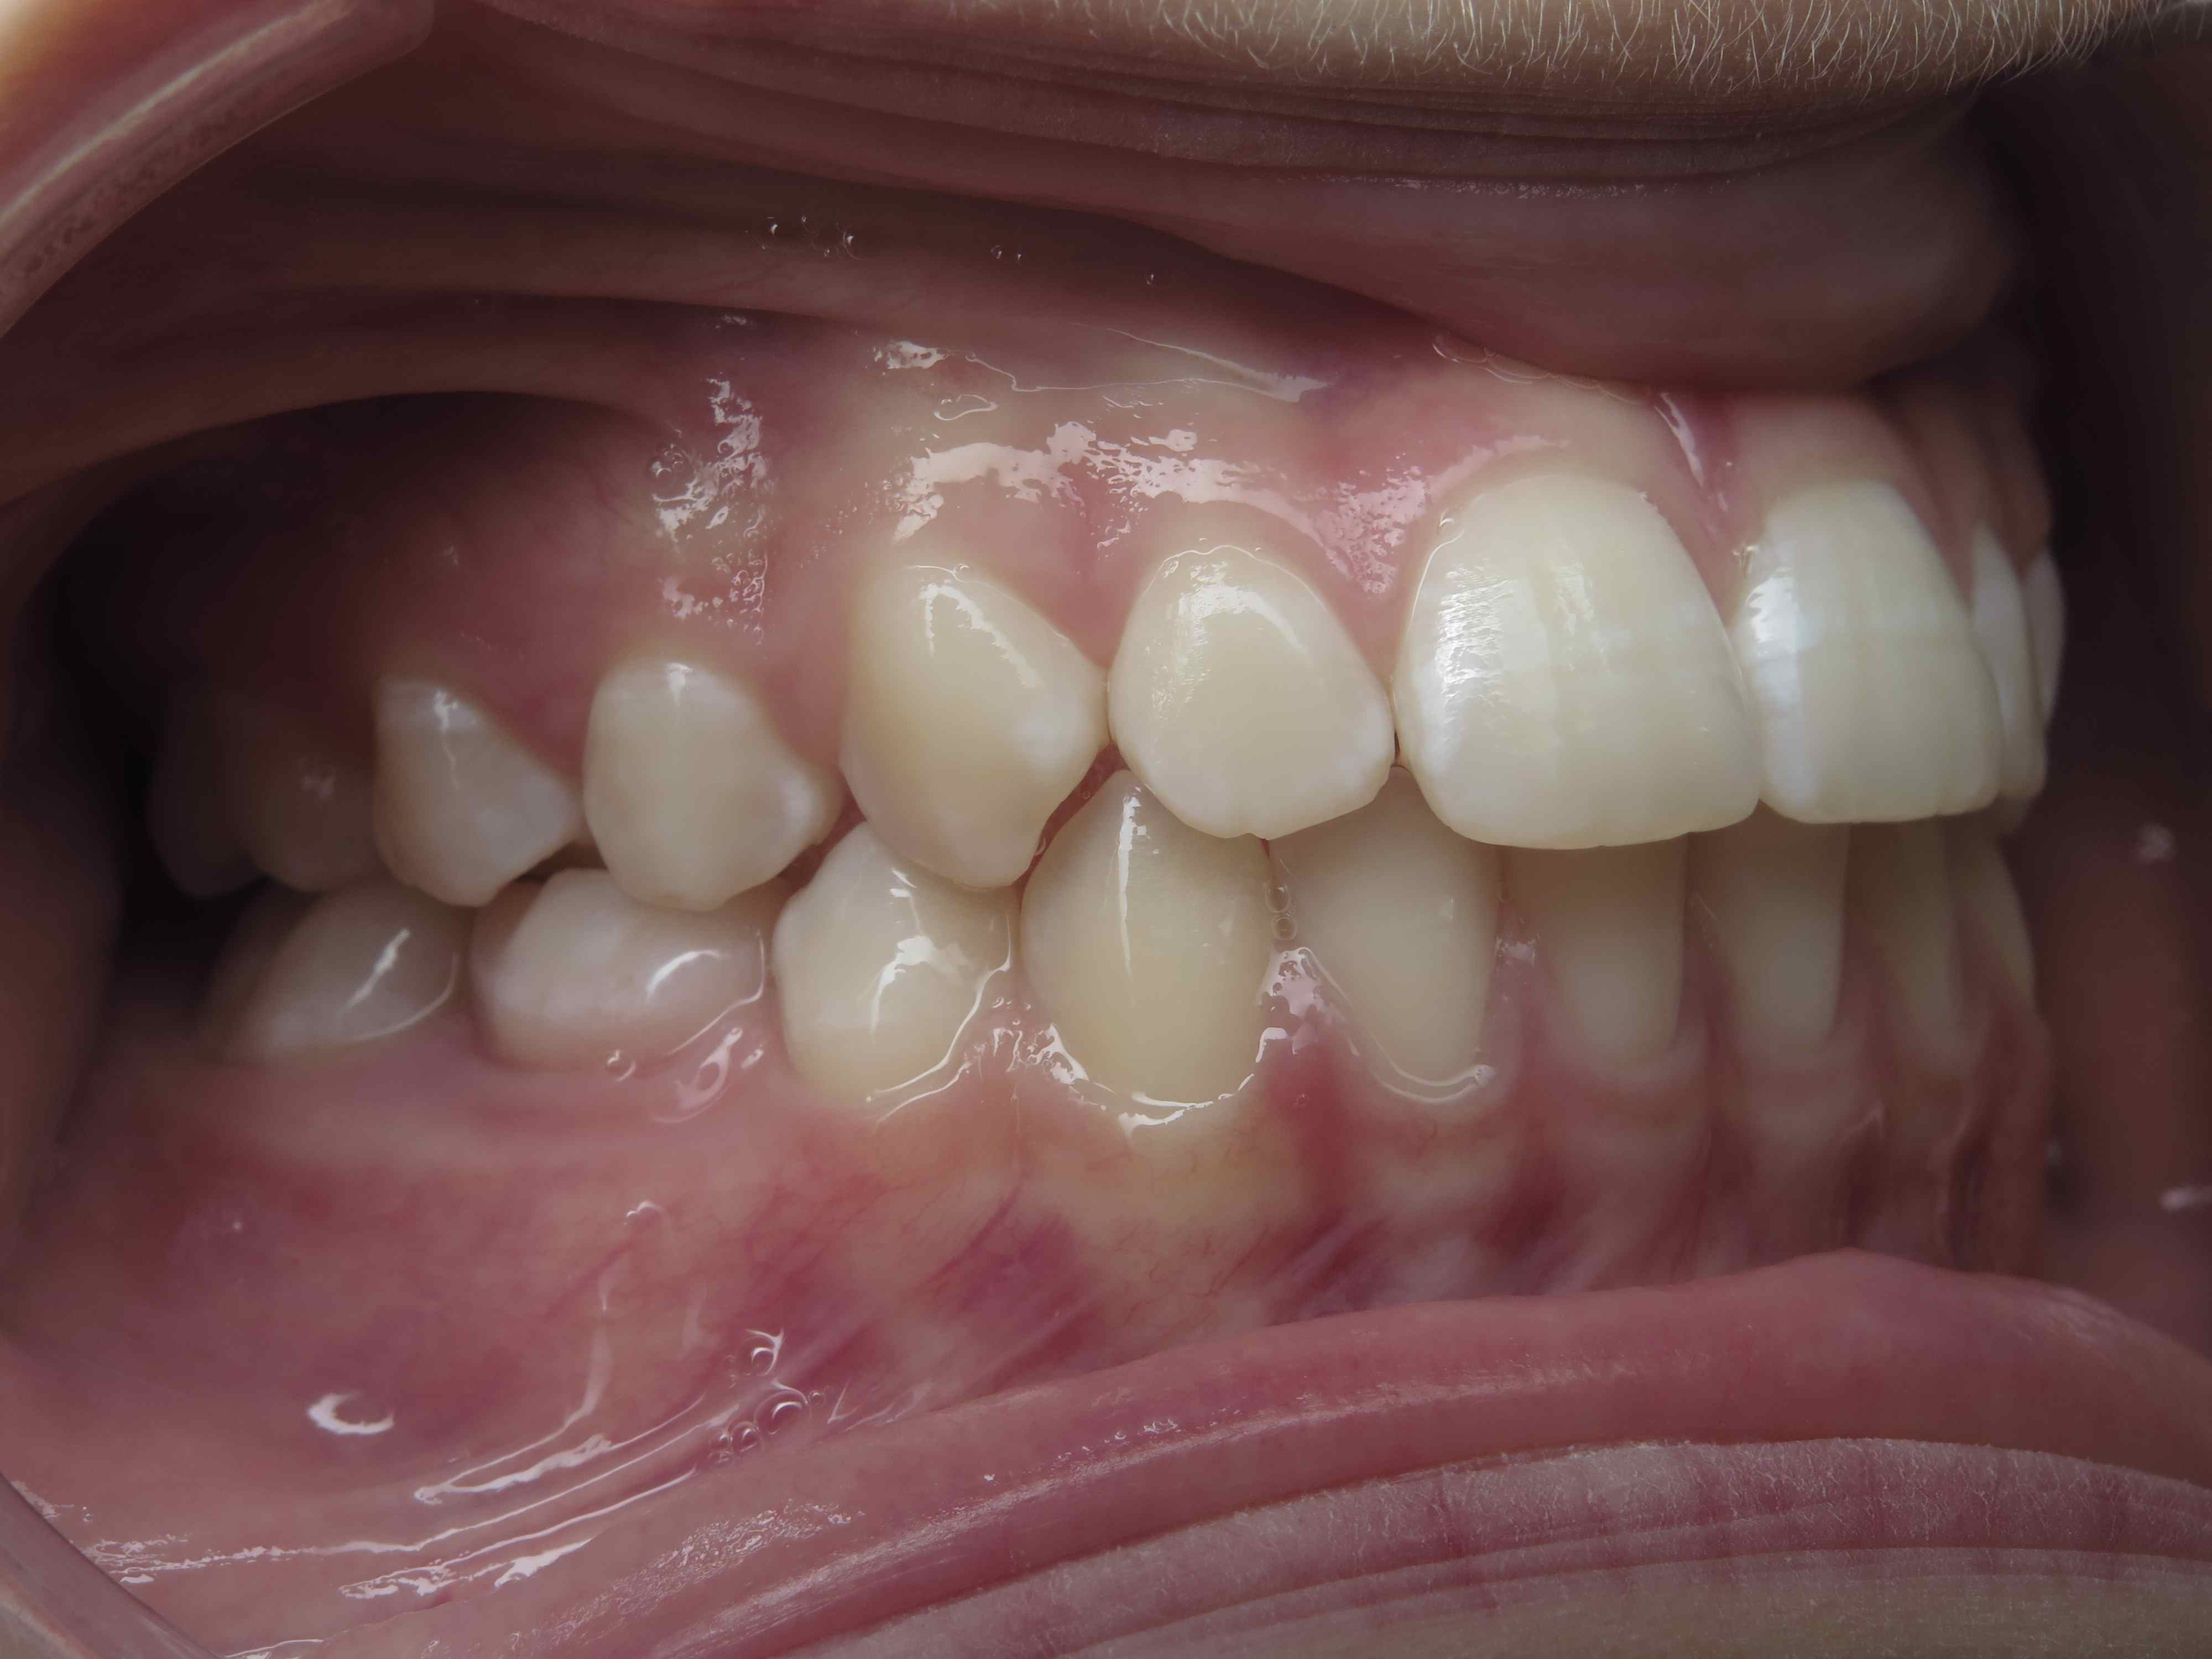

appareillage multibagues traitement en cours

bilan début et en cours de traitement